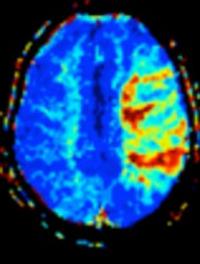

Une hypertension artérielle (HTA) est fréquente à la phase aigüe des accidents vasculaires cérébraux (AVC). Si plusieurs mécanismes [...]

Les accidents vasculaires cérébraux (AVC) sont la 2ème cause de mortalité dans le monde. Les hommes et les femmes sont sujets à différents [...]

L’encéphalopathie hypertensive est un dysfonctionnement cérébral aigu diffus, dû à une élévation majeure et brutale des chiffres tensionnels, [...]